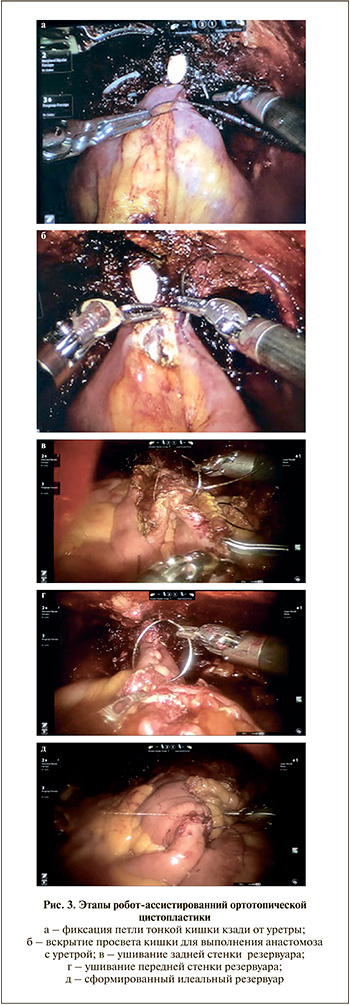

После удаления МП робот отсоединяли от портов, меняли положение Тределенбурга до 10–15°. Обратно подключали роботическую систему. Отступив более 25 см от илеоцекального угла, резецировали 40 см подвздошной кишки. Проходимость кишки восстанавливали анастомозом «бок в бок» аппаратным швом. Подвздошную кишку опускали в малый таз, подтягивая ее к уретре, помечали наиболее дистальную часть петли, которую фиксировали к парауретральным тканям сзади (рис. 3, а). В этой зоне вскрывали просвет кишки на протяжении 1,5 см, выполняли уретро-резервуарный анастомоз нитью 3/0 Stratafix и устанавливали катетер Фолея 20 Шр (рис. 3, б). Два дистальных участка используемой кишки по 15 см каждый укладывали U-образно, а проксимальную часть длиной 10 см оставляли тубулярной. Первые два сегмента детубуляризовали по антибрыжеечному краю, вначале непрерывным швом ушивали задние, далее передние края детубуляризованной кишки и заканчивали формирование резервуара (рис. 3, в–д). Левый мочеточник проводили через мезоколон сигмовидной кишки. Оба мочеточника имплантировали в тубулярный сегмент резецированной кишки по методу Nesbit, устанавливали double-J-стенты (рис. 4, а, б). В конце операции для проверки герметичности резервуара заполняли его стерильным раствором. В малый таз устанавливали дренаж, извлекали роботические инструменты и отсоединяли робот. Макропрепарат удаляли через расширенную троакарную рану.